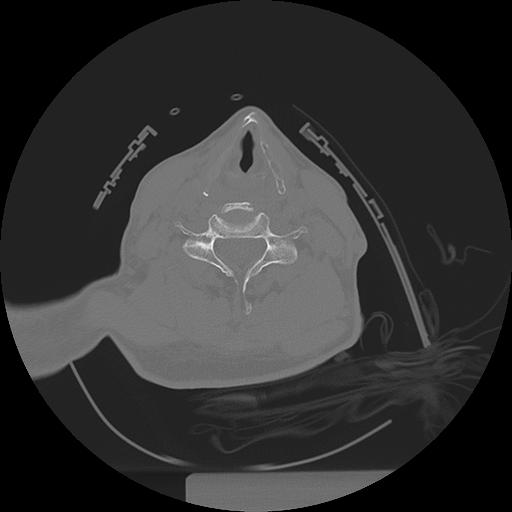

11 HUESO,,Axial,2.0,HUESO,,